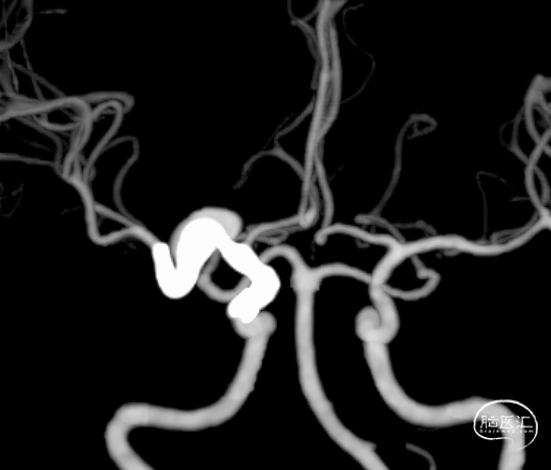

L ICA

Pre-OP

Post-OP

术后1周 颅脑CTA+CTP

影像随访:术后3月,颅脑CTA